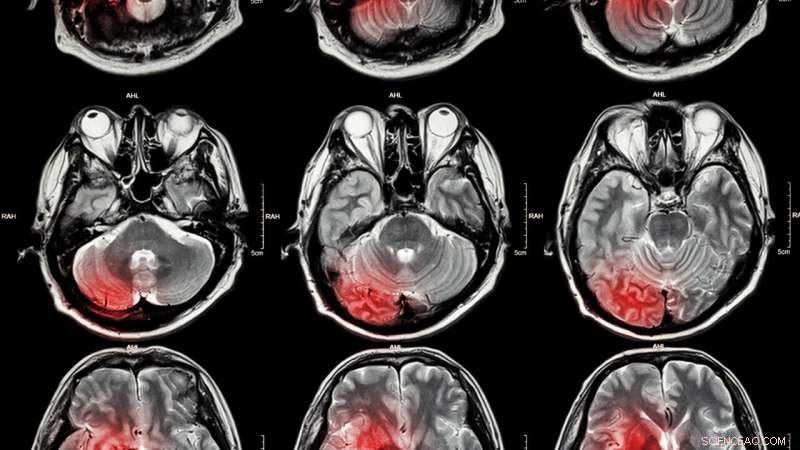

Stroke in adults linked to petroleum pollution. Credit: IOP Publishing